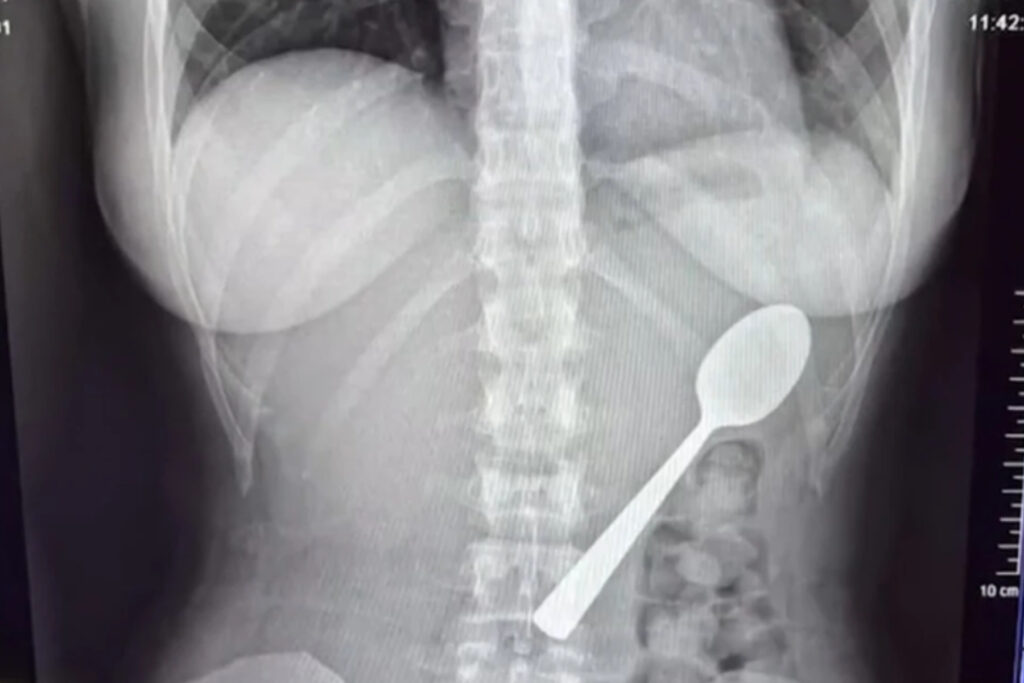

Μία 28χρονη γυναίκα κατάφερε να καταπιεί κουτάλι 17 εκατοστών και δεν είχε την παραμικρή ενόχληση. Μάλιστα αποφάσισε να επισκεφθεί τα επείγοντα ύστερα από παρότρυνση ανθρώπων από το διαδίκτυο.

Φαίνεται πως μία απίστευτη περιπέτεια έζησε μια νεαρή γυναίκα, καθώς κατάπιε ένα κουτάλι 17 εκατοστών, το οποίο κόλλησε στο στήθος της. Σύμφωνα με την ίδια δεν ένιωσε καμία ενόχληση και δεν ανησύχησε και νοσηλεύτηκε στα επείγοντα επειδή οι διαδικτυακοί της φίλοι…την συμβούλευσαν. Η ιστορία της έχει γίνει viral.

Γυναίκα κατάπιε κουτάλι 17 εκατοστών

Πιο συγκεκριμένα, η 28χρονη Reymy Amelinckx από το Βέλγιο έτρωγε γιαούρτι στον καναπέ της, όταν το σκυλάκι της, ο Μάρλεϊ, πήδηξε πάνω της. «Έβαλα το κουτάλι στο στόμα μου για να έχω τα χέρια μου ελεύθερα και να απαντήσω σε ένα μήνυμα. Ακριβώς εκείνη τη στιγμή, ο Μάρλεϊ αποφάσισε να πηδήξει πάνω μου», είπε.

«Τρόμαξα τόσο πολύ που έσκυψα το κεφάλι μου προς τα πίσω και, πριν το καταλάβω, το κουτάλι είχε κολλήσει στο λαιμό μου. Σηκώθηκα όρθια και άρχισα να πανικοβάλλομαι», είπε χαρακτηριστικά. Κι αφού δεν μπορούσε να αφαιρέσει το κουτάλι, η Reymy είπε ότι αναγκάστηκε να πάρει μια απόφαση σε κλάσματα δευτερολέπτου. Τελικά το κατάπιε και δεν είπε τίποτα στον φίλο της όταν επέστρεψε σπίτι, επειδή ντρεπόταν.

«Δεν ένιωθα καμία ενόχληση, οπότε δεν ανησύχησα», δήλωσε και σημείωσε ότι άρχισε να ρωτάει στο διαδίκτυο για την κατάστασή της. Τότε, με όσους χρήστες επικοινώνησε, την προέτρεψαν να πάει στο νοσοκομείο, τονίζοντας ότι είναι σοβαρό. Η 28χρονη παρότι δεν ένιωθε κάτι, πήγε στα επείγοντα και εκεί οι γιατροί έμειναν άναυδοι.

Αρχικά, προσπάθησαν να τραβήξουν έξω το κουτάλι, όμως ήταν αρκετά μεγάλο για να βγει φυσιολογικά, οπότε προχώρησαν σε γαστροσκόπηση. «Εκείνη η νύχτα ήταν δύσκολη, ένιωθα το κουτάλι να κινείται, μερικές φορές ακόμη και ανάμεσα στα πλευρά μου. Ήταν πραγματικά τρομακτικό. Ένιωθα φουσκωμένη και ναυτία, και δεν μπορούσα να φάω χωρίς να νιώθω περίεργα. Ο ύπνος ήταν δύσκολος, γιατί κάθε στάση μου θύμιζε το κουτάλι στο στομάχι μου», είπε η Reymy.

Εν τέλει, το κουτάλι αφαιρέθηκε σε προγραμματισμένο χειρουργείο μετά από δύο μέρες, με τη γυναίκα να προειδοποιεί τον κόσμο μετά την περιπέτειά της να ζητούν πάντα ιατρική συμβουλή, ακόμη και αν δεν αισθάνονται κάποια ενόχληση.